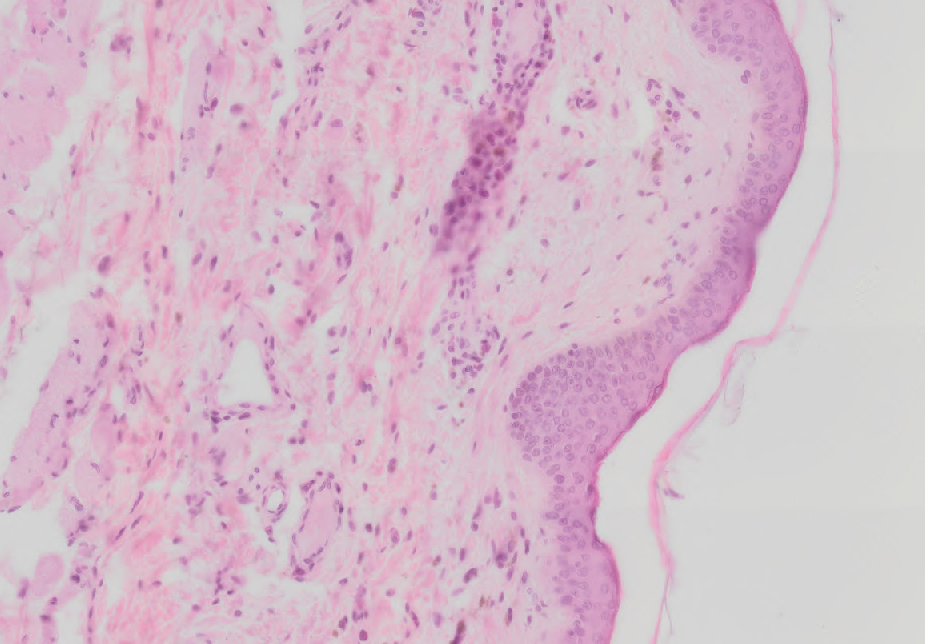

14 Na snímku je tenký typ kůže barvený hematoxylinem eosinem. Co je tenká eosinofilní linie probíhající nad epitelem v pravé části preparátu?

Kuze tenky typ.png

Zbytek oděvu, který zůstal na těle při příliš rychlém zpracování preparátu

Kompletní stratum corneum, u tenkého typu kůže jde jen o vrstvu 2-4 buněk

Nekompletní stratum corneum, při zpracovnání často velká část odpadne

Artefakt z barvení